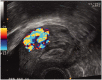

Ultrasound assessment of the postpartum uterus has a significant role to play in the evaluation of a large proportion of symptomatic puerperal women. Often the imaging modality of choice for excluding retained placental tissue, correct application of postpartum ultrasound could enable more accurate identification of women requiring surgical intervention, with consequent reduction in patient morbidity and clinical workload. This article aims to review the current understanding and application of ultrasound in the puerperium and evaluate the current evidence investigating the physiological and pathological findings of the postpartum uterus and its contents.